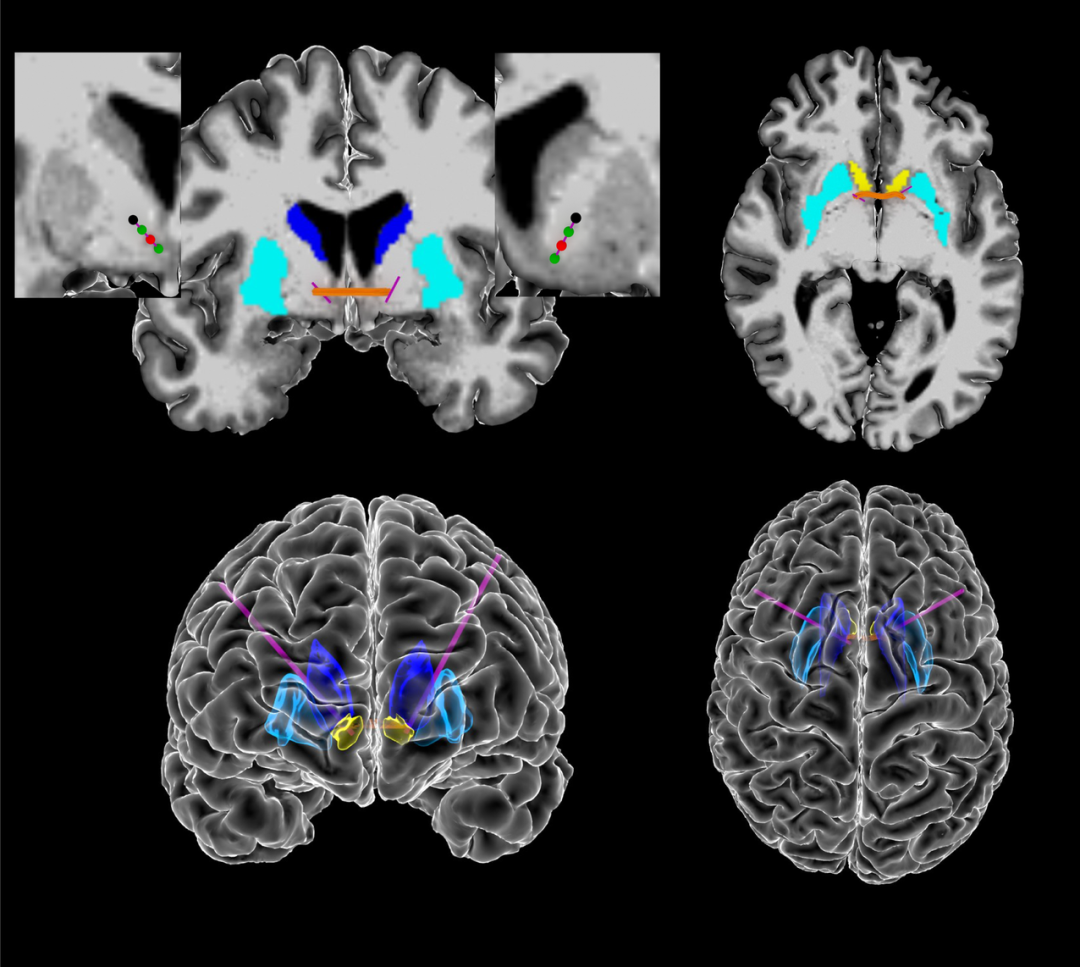

图 | 颅内电生理数据的采集(来源:Nature

为此,Borton 教授带领的研究团队招募了 5 名接受深部脑刺激治疗的重度强迫症患者进行试验,收集强迫症患者的脑电波活动,同时利用视频记录患者的生活和行为,并利用人工智能评估患者各种微妙的情绪变化,并与脑电波活动相匹配。

与以往的经验不同,强迫症的大脑信号不仅仅来自于大脑腹侧内囊/腹侧纹状体 ,也来自于大脑皮质-纹状体-丘脑-皮质环路。 除了脑电波信号,研究人员还收集了一套强迫症患者行为的生物标志物,包括面部表情和身体运动。通过人工智能,他们发现这些行为和特征与大脑内部信号变化密切相关。

图 | 大脑深部刺激的作用示意(来源:Nature